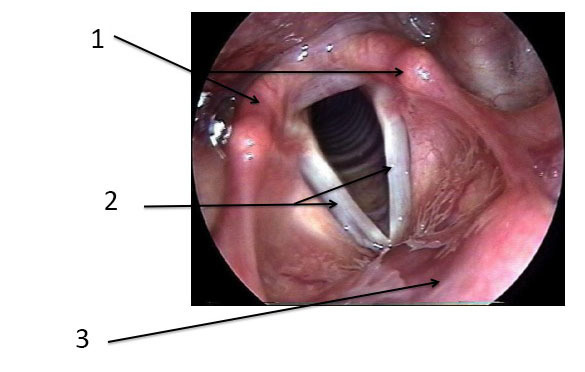

Vous faites un examen sous anesthésie générale : une pan-endoscopie. En dehors de la lésion du bord de langue gauche, tout semble normal.

Question 9 : Vous constatez notamment les structures anatomiques suivantes, quelles sont-elles ?

Le cricoïde est un anneau circulaire cartilagineux sur lequel repose les deux cartilages aryténoïdes. En dessous du cricoïde commencent les anneaux trachéaux

Cartilage paire et symétrique, dont la mobilité assure le mouvement des cordes vocales

Glotte ou plan glottique : ce sont les cordes vocales

Deux cordes vocales normales, avec commissure antérieure

C’est la face postérieure de l’épiglotte. On peut la repérer car elle est juste en avant de la commissure antérieure des cordes vocales

L’anatomie du larynx est importante à connaître dans les grandes lignes. La glotte est un synonyme de plan glottique et de cordes vocales.